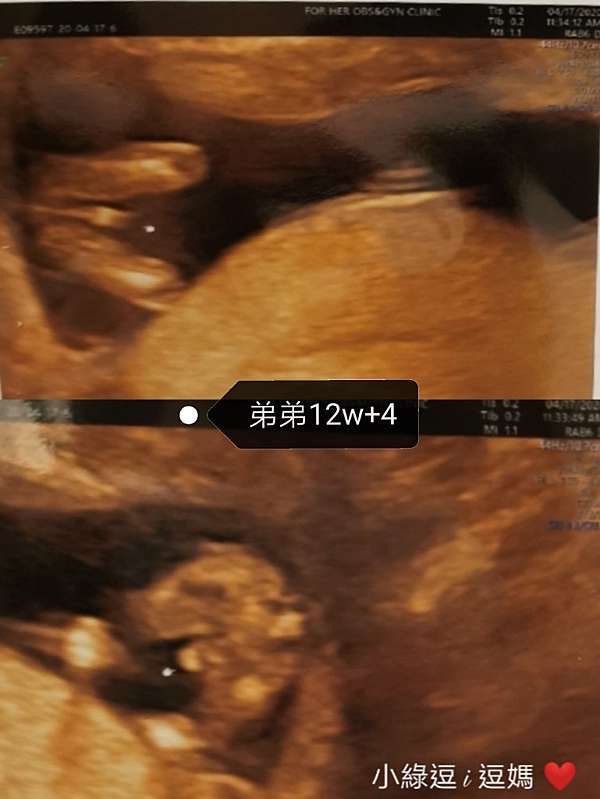

二寶日記 12w 4 開獎日 男孩女孩一樣好兩胎初期症狀比較 小綠逗i逗媽 痞客邦